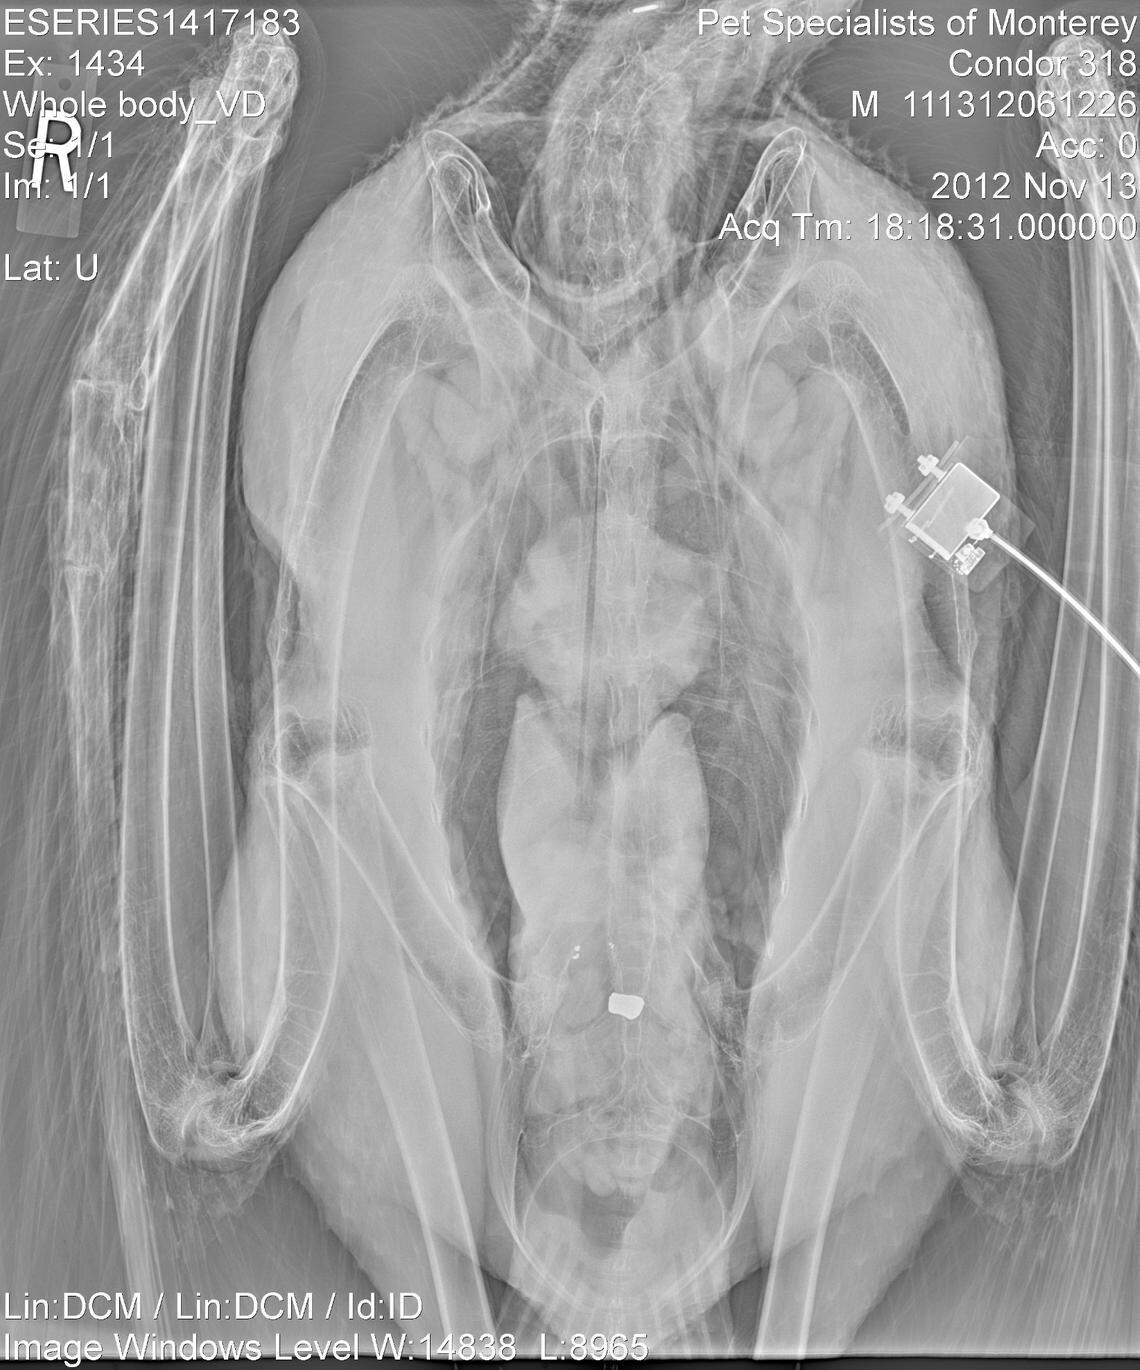

This lead bullet was ingested by condor #318, Benito, a reproductive male, after he consumed carrion. Benito died from lead poisoning on Nov. 30, 2012.

An x-ray of Condor #318, Benito, taken on Nov. 13, 2012, shows lead fragments and a bullet.